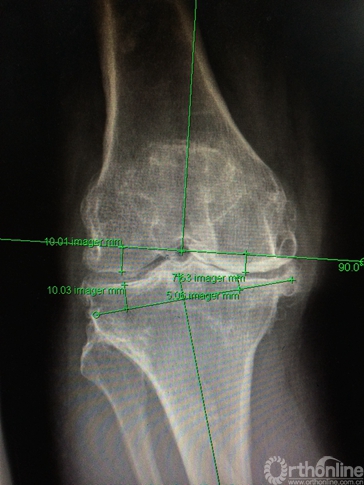

图2b. 确定截骨的厚度。

图3a.股骨远端模型及股骨侧截骨导板。

图3b. 胫骨近端模型及胫骨侧截骨导板。